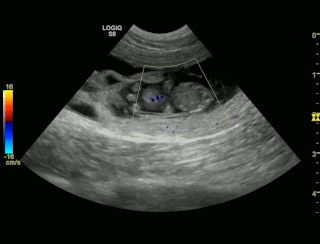

Sookie und Uaine erwarten Babies! Die Ultraschallbilder beweisen es! Hier sind die Bilder!!! |

| Hier sind die Ultraschallbilder von Sookie von Waltenweiler!!! |